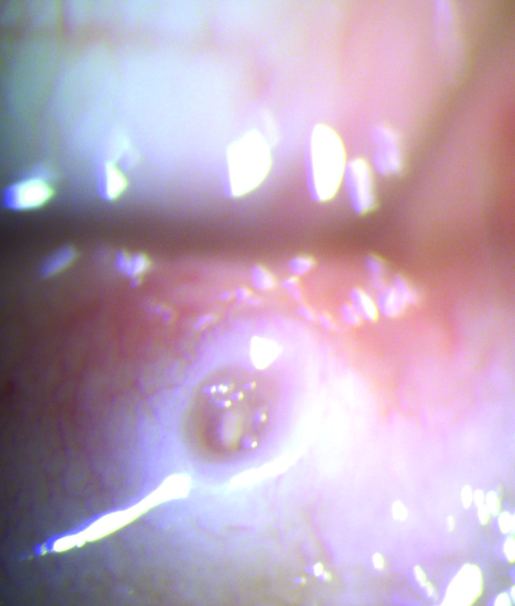

Otro factor a tener en cuenta dentro de la problemática del uso de los tapones lagrimales es el cambio anatómico que se produce en la estructura del punto lagrimal. Dilatación, edema, reacciones papilares, inflamación y fibrosis son frecuentes hallazgos (Fig. 26).

Figura 26: Cambios anatómicos en el punto lagrimal al retirar los tapones.